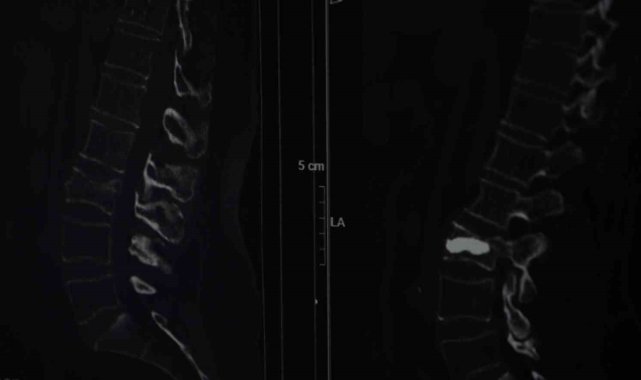

İstanbul'da yaşayan 76 yaşındaki kadın, iddiaya göre düşme sonrası hissettiği ağrıları fıtığa bağladı, hastaneye gittiğinde ise omurgasında kırık olduğunu öğrendi. Yaşlı kadın, başarılı operasyonla sağlığına kavuşurken, uzmanlar ilerleyen yaşlarda kemik erimesine karşı uyardı. Beyin ve Sinir Cerrahisi Uzmanı Doç. Dr. Şevket Evran, "Omurga kırıklarını menopoz sonrası bayanlarda sıklıkla görüyoruz. Türkiye hatta dünya genelinde bu tarz hastalar çok fazla. Bel fıtığından şüphelenerek ağrılarının ona bağlı olduğunu düşünmüş, dinmeyince hastanemize başvurmuş. Menopoz sonrası bayanlar mutlaka kemik yoğunluğuna baktırmalı" dedi. Yaşlı kadın ise "Düştüm, hiçbir yerimde ne çizik ne morartı vardı, 2 tane fıtığım var, nüksetti dedim. Ağrılar, geçmeyince doktora gittik, operasyon sonrası hemen ayaklandım" diye konuştu.İstanbul'un Sarıyer ilçesinde Kilyos'taki evinde tek başına yaşayan 2 çocuk annesi emekli mali müşavir olan 76 yaşındaki Alis Armağan, iddiaya göre ağustos ayında evinin bahçe kapısının önünde düştü. Düşme sonrası omurganın bel bölgesinde kırık meydana geldi ancak Armağan ağrılarını bel fıtığına bağladı. Bir süre bu şekilde düşünen Armağan, ağrıları geçmeyince Şişli Hamidiye Etfal Eğitim ve Araştırma Hastanesi'ne başvurdu. Burada Beyin ve Sinir Cerrahisi Uzmanı Doç. Dr. Şevket Evran ve ekibinin yaptığı incelemelerde kemik erimesine bağlı kırık tespit edildi. Armağan, durumu şaşkınlıkla karşılarken doktorlar operasyon gerekliliğini ifade etti. Genellikle kemik erimesine bağlı omurga kırıklarını tedavi etmek amacıyla uygulanan minimal invaziv bir cerrahi yöntem olan ve hastanın aynı gün normal yaşamına dönebilme imkanı sunan kifoplasti operasyonu 25 Ağustos günü gerçekleştirildi. Doç. Dr. Evran ve ekibinin yaptığı operasyon başarılı geçerken Armağan da rahat bir nefes aldı. Doç. Dr. Evran, özellikle menopoz sonrası kadınlarda kemik erimesi kaynaklı oluşan kırıklarına dikkat çekerken tedavilerine ilişkin bilgi verdi, vatandaşlara önemli uyarılarda bulundu."Fıtık diyerek oyalandım, ameliyat öncesi perişandım"Yaşadıklarını anlatan 76 yaşındaki Alis Armağan, "Bahçe kapısının önünde düştüm, ne olduğumu anlayamadım. Hiçbir yerimde ne çizik ne morartı var, öyle bir düşme. Herhalde 2 tane fıtığım var, düşmeyle onlar yine nüksetti dedim. İğneler oldum, geçmeyince bu başka bir şey diyerek doktora müracaat ettik. Hemen de ayaklandım, Allah'a şükür, her gün doktoruma dua ediyorum. Allah kimseye böyle sıkıntılar vermesin, hele ileri yaş için çok zor. Düşmem ağustos başıydı, ameliyat 25 Ağustos'ta oldu, fıtık filan diyerek oyalandım. Sonra MR çekildik, tespit edildi. Yoksa ameliyat öncesi perişandım. Bu yaştan sonra ameliyat mı olur dedim, herkes de yaşlılar çok zor, çok riskli diyor. Hastaneye çok umutsuz geldim ama iyi çıktım" diye konuştu."Omurga kırıklarını menopoz sonrası bayanlarda sıklıkla görüyoruz""Omurga kırıklarını menopoz sonrası bayanlarda sıklıkla görüyoruz" diyerek sözlerine başlayan Doç. Dr. Evran, "Bu hastalarda travma sonrası kemik yoğunlukları düşük olduğu için omurgalarında kırık oluşma ihtimali normal popülasyona göre çok daha fazla görülüyor. Travma geçiren menopoz sonrası bir insanda kemik yoğunluğuna daha önce dikkat etmemiş, bununla ilgili daha önce tedavi almamışsa bu hastalarda travma sonrası oluşan, bel, sırt, boyun ağrılarında özellikle bu kırıklar düşünülmekte. Bir beyin ve sinir cerrahisi hekimine başvurmaları önerilmekte. Vücudun daha çok yük taşıyan bel ve sırt bölgelerinde oluşuyor. Hasta sırt veya bel ağrısıyla travma sonrası başvurduğu zaman önce gerekli tetkiklerini yapıyoruz. Görüntülemelerinde kırığı tespit etmiş olursak ve bu bir travma sonrası gelişen bir kırıksa bu kırıkta öncelikle omurgadaki çökme miktarının derecelerine bakıyoruz. Derecelere göre korse, yatak istirahati gibi tedavileri öncelikle deniyoruz. Fakat kırığın çökme derecesi çok ileriyse veya omuriliğe bir zarar söz konuysa daha minimal invaziv olarak tedaviler ve daha ileri hastalarda cerrahilerle omurgaya enstrümantasyonlarla tedavi edebiliyoruz" dedi."İğnenin geçtiği kadar delikten sıvı olan sonra katılaşan bir maddeyi enjekte ediyoruz"Tedavi seçeneklerine yönelik konuşan Doç. Dr. Evran, "Hastanın klinik durumu uygunsa vertebroplasti veya kifoplasti dediğimiz halk arasında omurgaya çimento doldurma olarak bilinen işlemi bu hasta grubunda uygulamak öncelikli tercihimiz oluyor. İşlemin bazı avantajları var; eskiden bu tarz kırıklarda hastaları günlerce yatakta yatırıp hatta tüm vücut alçıya alınıp tedavi edilirmiş ama günümüzde teknolojinin de ilerlemesiyle artık bu yöntemler daha ön planda. Vertebroplastide hastanın cildinde büyük bir kesi olmadan sadece bir iğnenin geçtiği kadar bir delikten iğne yardımıyla girilerek omurganın içine bazen tek bazen çift taraflı girilerek başlangıçta içinde sıvı olan sonra katılaşan bir maddeyi enjekte ediyoruz. Omuriliğin içinde donuyor. Başka bir yöntemi olarak da bazen omurganın içinde bir balon yardımıyla balon şişirerek omurganın eski yüksekliğini kazanmasına ve daha güvenli bir alan oluşturarak balonun şiştiği alana çimento dediğimiz şeyle doldurarak hastanın da ağrılarının geçmesini sağlamış oluyoruz, akşamına hasta taburcu edilebiliyor" diye konuştu."Türkiye hatta dünya genelinde bu tarz hastalar çok fazla"Sözlerini sürdüren Doç. Dr. Evran, "Bu tarz hastalar kliniğimize çok başvuruyor sadece kliniğimize değil Türkiye hatta dünya genelinde bu tarz hastalar çok fazla. Bu cerrahiyi uyguladığımız ayda ortalama 4 ila 5 hasta. Bu hastamızda bir travma sonrası bel omurgasında kırık meydana gelmiş, ilk planda kırık olarak algılamıyor, şiddetli ağrılardan vücudunda kötü bir şey geliştiği yönünde bir kanaate varmış. Ameliyat sonrası 4'üncü saat, ayağa kalkarak yürümesini sağladık. Osteoporoz olan hastalarda omurga kırıklarını önlemenin yollarından bir tanesi de menopoz sonrası bayanların mutlaka kemik yoğunluğuna baktırması gerekiyor. Hastalar bu tarz travmalardan sonra ağrılarını birçok şeye yorabiliyor. Özellikle bel fıtığı, belinde kas güçsüzlüğü, düzleşme gibi hastamız da önce bel fıtığından şüphelenerek ağrılarının ona bağlı olduğunu düşünmüş fakat dirençli bir ağrı. Hiçbir medikal tedavi, ilaçla ağrıları dinmeyince durumun daha farklı boyutta olduğunu düşününce hastanemize başvurmuş" dedi.